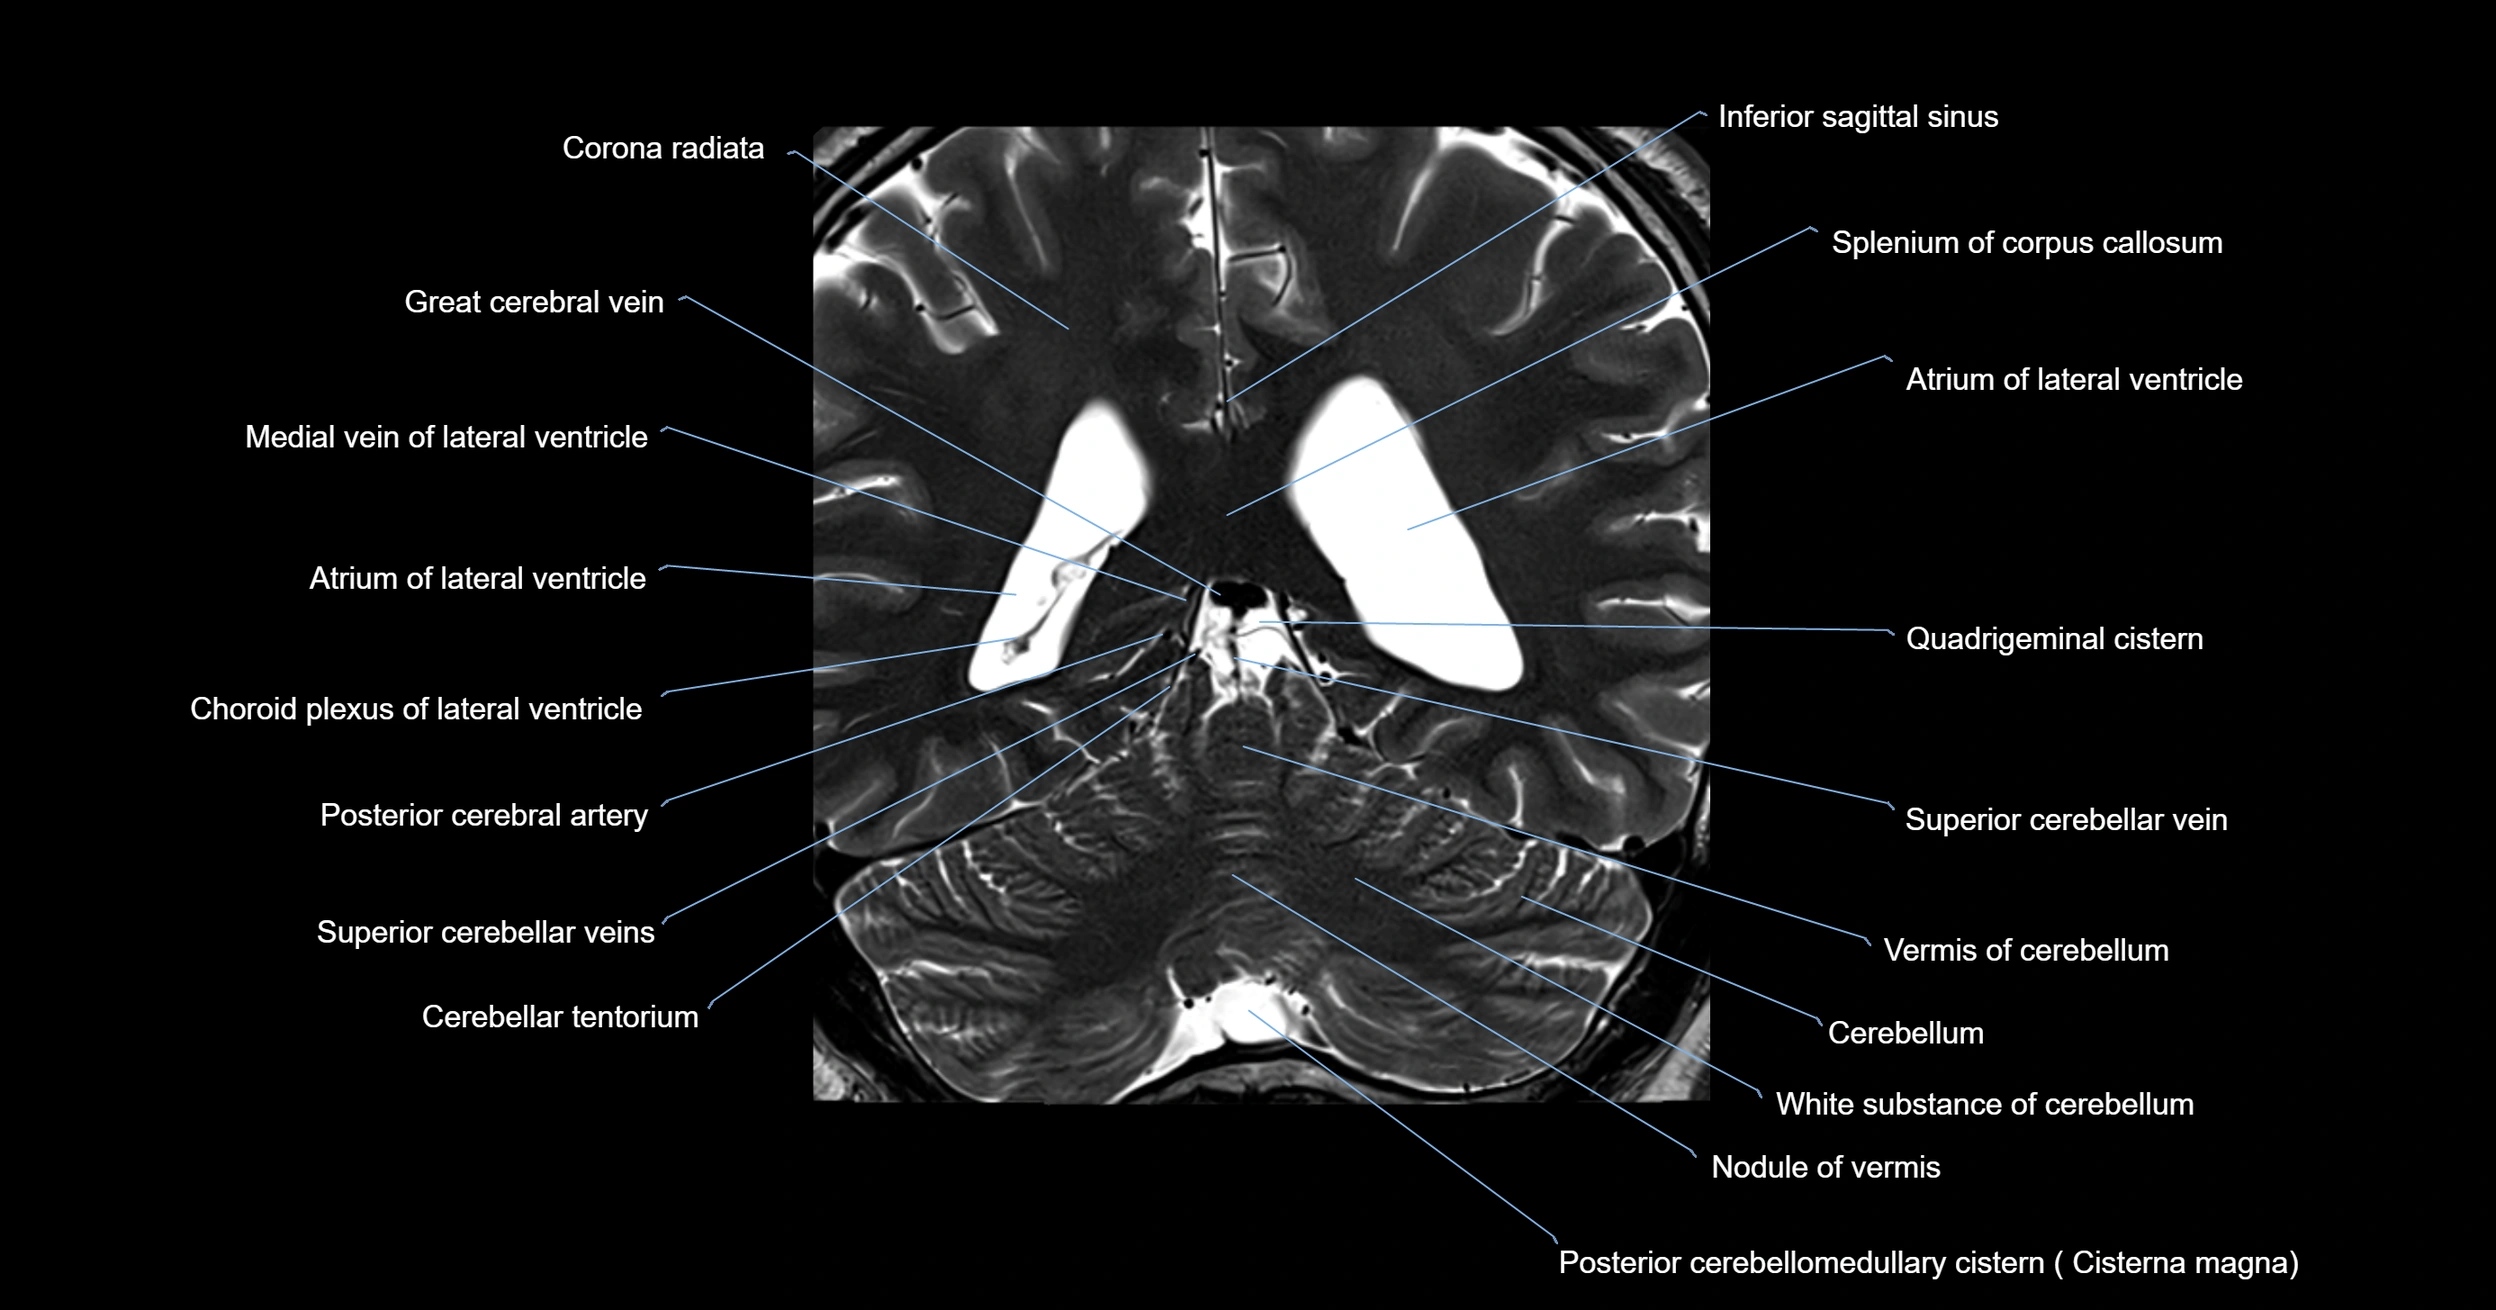

- Atrium of lateral ventricle

- Cerebellar tentorium

- Cerebellum

- Corona radiata

- Great cerebral vein

- Inferior sagittal sinus

- Medial vein of lateral ventricle

- Nodule of vermis

- Posterior cerebellomedullary cistern (cisterna magna)

- Posterior cerebral artery

- Precentral cerebellar vein

- Quadrigeminal cistern

- Splenium of corpus callosum

- Superior cerebellar vein

- Superior vein of vermis

- Vermis of cerebellum

- White matter of cerebellum (Arbor vitae)

- White substance of cerebellum